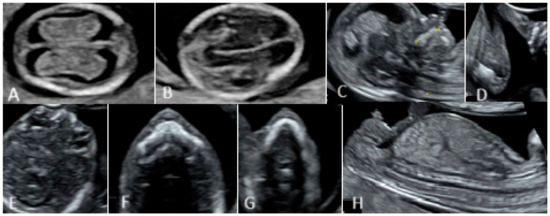

2.1. First Trimester Scanning and Sections

2.2. Second Trimester Scanning and Sections